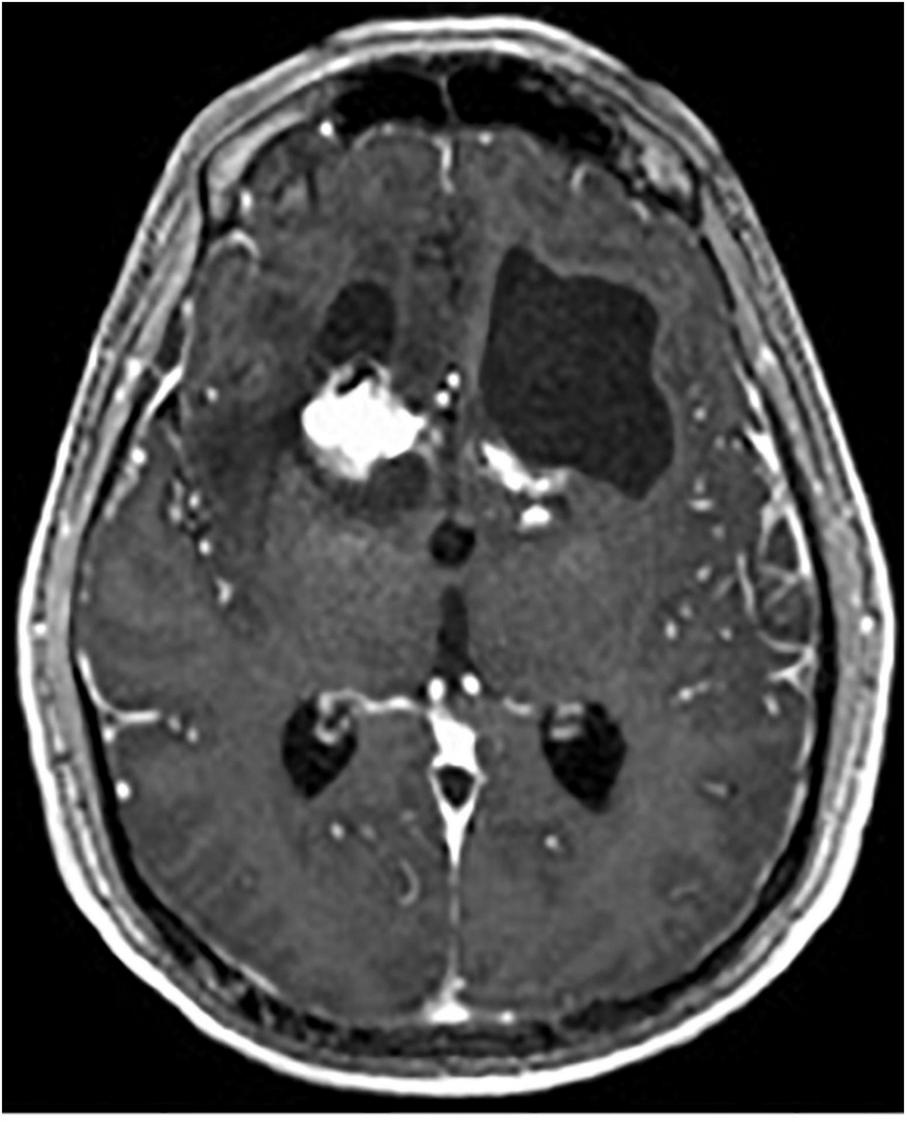

One complication of radiosurgical capsulotomy is the development of brain cysts, which have been found in 10% of patients at 5-year follow-up (Peker et al., 2020). They appear to be a radiation dose-dependent phenomenon, with doses above 140 Gy predicting occurrence, whereas lower doses of 110 Gy appear to be safe (Kihlström et al., 1997; Kasabkojian et al., 2021; Figure 9).

FIGURE 9

Axial T1-weighted MRI with contrast of brain cyst in the left hemisphere after gamma knife capsulotomy.